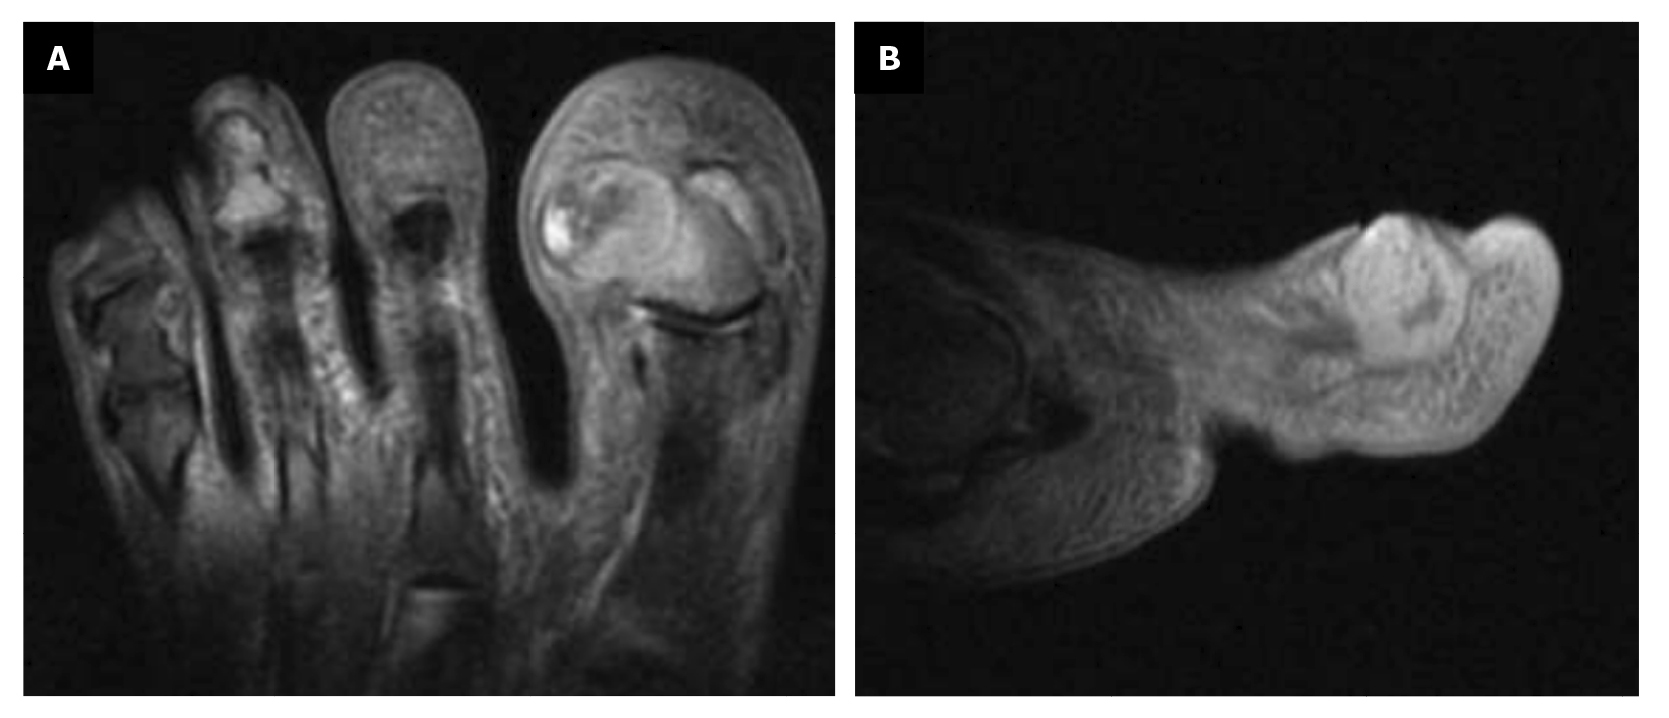

En el transcurso de 3 semanas después de la tercera intervención, la paciente refiere recidiva de la lesión y de la sintomatología dolorosa (Figura 7). La paciente decide acudir a servicio de traumatología (febrero de 2023) donde se solicita la realización de resonancia magnética nuclear (T2FS y DPFATSAT). En ella, se aprecia masa ocupante en el tercio lateral del primer dedo con bordes bien definidos y afectación ósea (Figura 8) con el siguiente informe: “A nivel de la falange distal del primer dedo en la región ungueal impresiona solución de continuidad cutánea con colección heterogénea, densa de 15 mm × 14 mm que se ubica en la región lateral de partes blandas parafalángicas, remodela el hueso y se pone en contacto con el tendón flexor, pudiera corresponderse con absceso/colección flemonosa postquirúrgica. Impresiona algo de edema óseo en falange distal sin descartar completamente incipiente osteomielitis. A confrontar con antecedentes y protocolo quirúrgico realizado”.

Figura 8. Masa ocupante con afectación ósea; A: plano transverso; B: plano sagital.